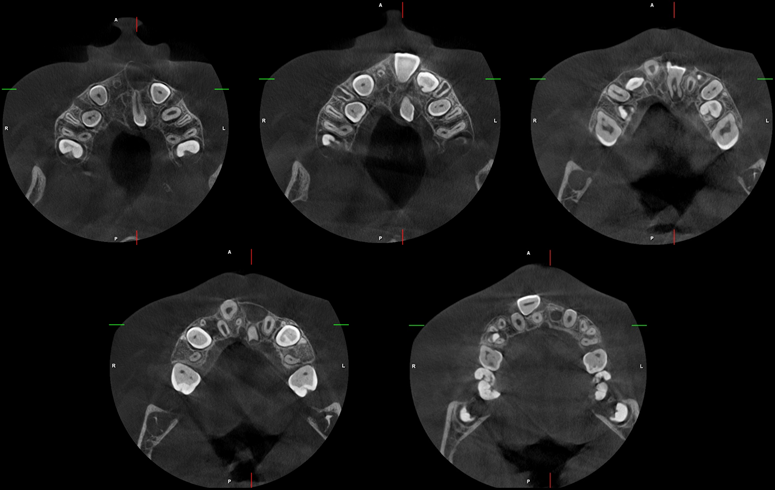

A la evaluación de la tomografía computarizada se puede observar con más claridad el supernumerario denominado “A” de forma rudimentaria que se encuentra por palatino de la pieza 11 y que contacto con la cortical del agujero nasopalatino, asimismo observamos la pieza 21 con la porción coronaria en contacto con la tabla ósea vestibular adelgazándola; finalmente y como hallazgo imagenológico se encontró un segundo supernumerario denominado “B” que se localiza cefálico a la pieza 21 también en posición transversal pero con la porción coronaria en contacto con la tabla ósea palatina y el piso de fosa nasal y finalmente el tercio apical se e en contacto con

la región cervical de la pieza 21.

CORTES AXIALES